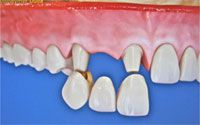

Фото. Имплантат, абатмент, коронка.